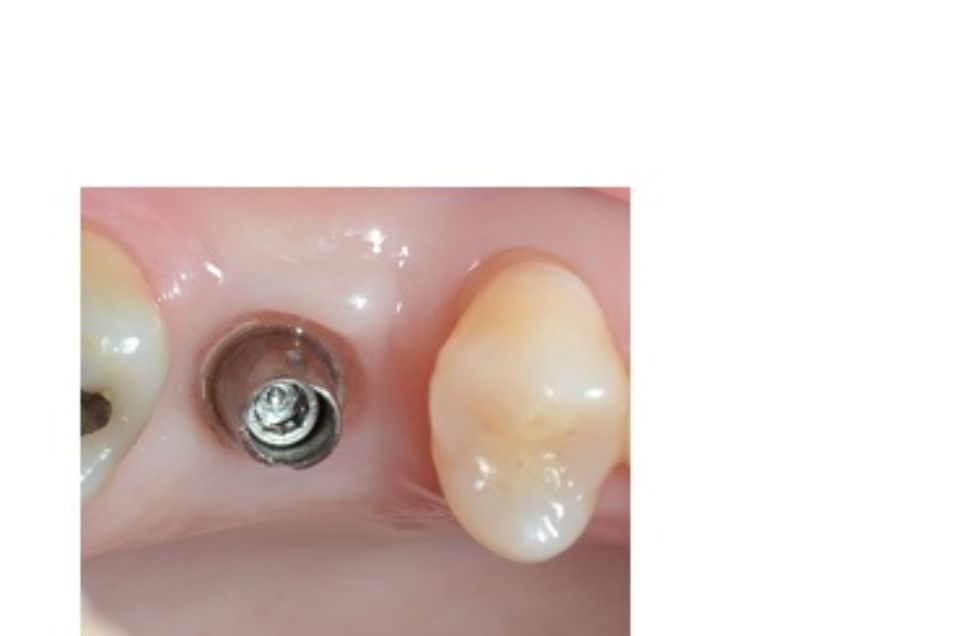

Implantologia bucal

La implantologia és l´especialitat odontològica que s´ocupa de la substitució de l´arrel de la dent perduda.

La substitució es fa mitjançant una petita intervenció quirúrgica per col·locar una peça de titani dins de l'os maxil·lar.

L'implant té una rosca al seu interior on posteriorment s'enroscarà el pilar que suportarà la corona protètica.